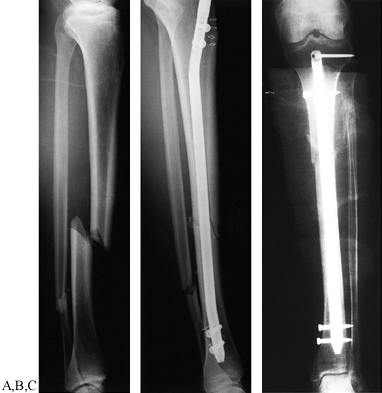

Figure 24.5. Radiographic examples of the four grades of tibial fracture severity. A: Minor severity: spiral fracture caused by a simple slip and fall. B: Moderate severity: transverse fracture in a pedestrian struck by slowly moving vehicle. C: Major severity: comminuted fracture with tibial-fibular diastasis caused by a high-velocity motorcycle crash. D: Major severity: near amputation caused by a high-speed motorcycle accident; with segmental bone loss.